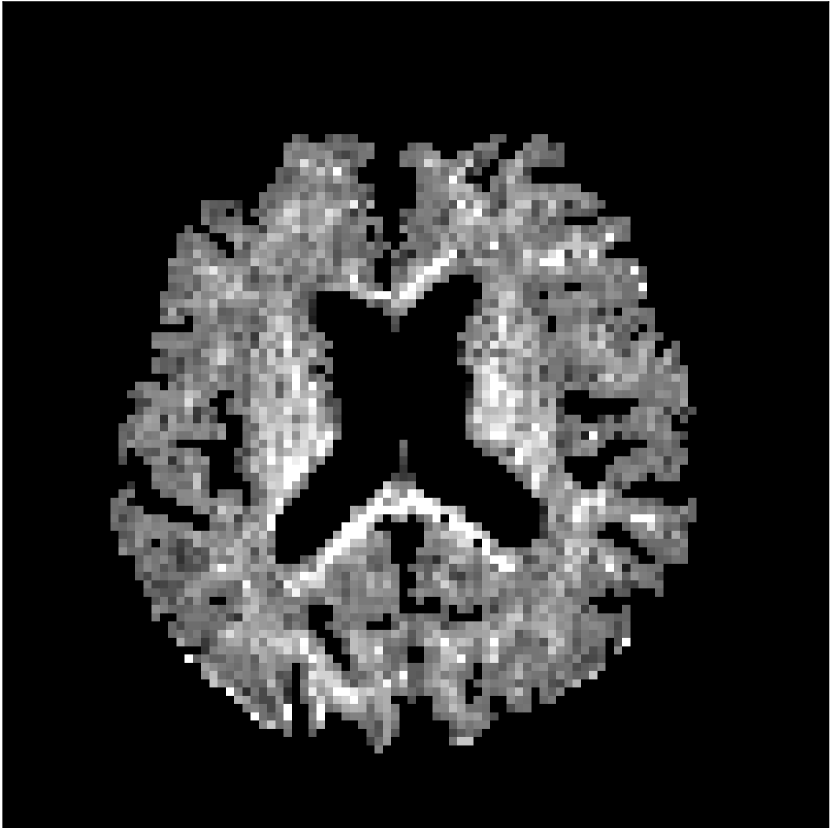

Figure 10 compares mean diffusivity maps across various partial Fourier factors between the CCNN and state-of-the-art methods.

No PF

7/8 PF

6/8 PF

5/8 PF

SoA

MD, m2/ms

CCNN

The methods perform similarly without partial Fourier acceleration, but as partial Fourier acceleration increases, the image is continually degraded in the SoA method, with "black voxels" appearing around the lateral ventricles. The CCNN method mitigates the appearance of these artifacts in the parameter maps.